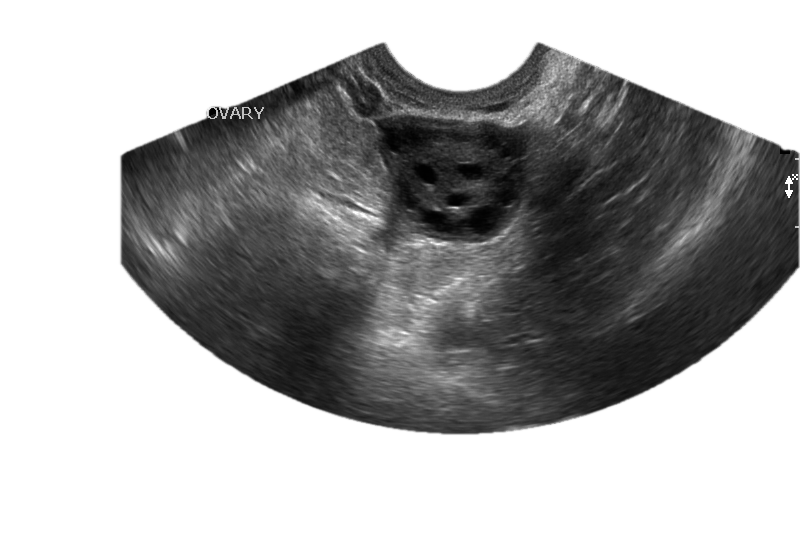

Point-of-care ultrasound — ovary

POCUS Assessment 11 Sections

EM Ultrasound Post-Test

Comprehensive EMUS post-test covering Physics, FAST, Pneumothorax, OB/GYN, Aorta/AAA, Soft Tissue, Vascular/DVT, Gallbladder, Renal, Cardiac, and Knobology. Scored with feedback.